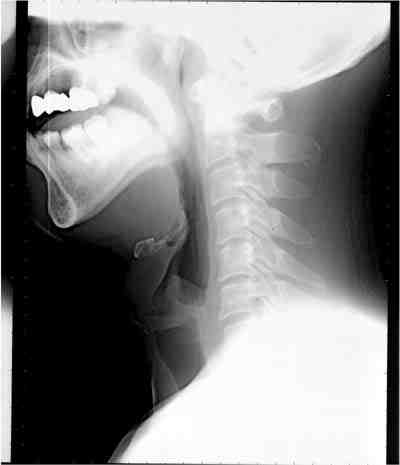

Sleep splint(口腔内装具)の効果

装具装着前

装具装着後

下顎が前方に移動し,気道が広くなっています。(黒い部分が空気の通り道です。)